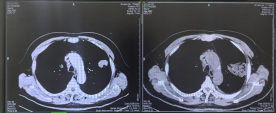

综合考虑患者病情及既往治疗情况,介入医学科团队经充分评估后,决定为其施行氩氦刀冷冻消融治疗。术中,通过CT引导精准定位病灶,利用高压氩气迅速降温至零下140℃以下,使肿瘤细胞内冰晶形成、细胞膜破裂,继而通过氦气快速复温至20℃–40℃,完成“冻融”循环,导致肿瘤组织不可逆坏死。术后影像显示病灶密度明显减低,肿瘤实性组织轮廓消失。患者术后未再出现痰中带血,恢复顺利,已于近期出院。

消融前后对比

术前术后对比